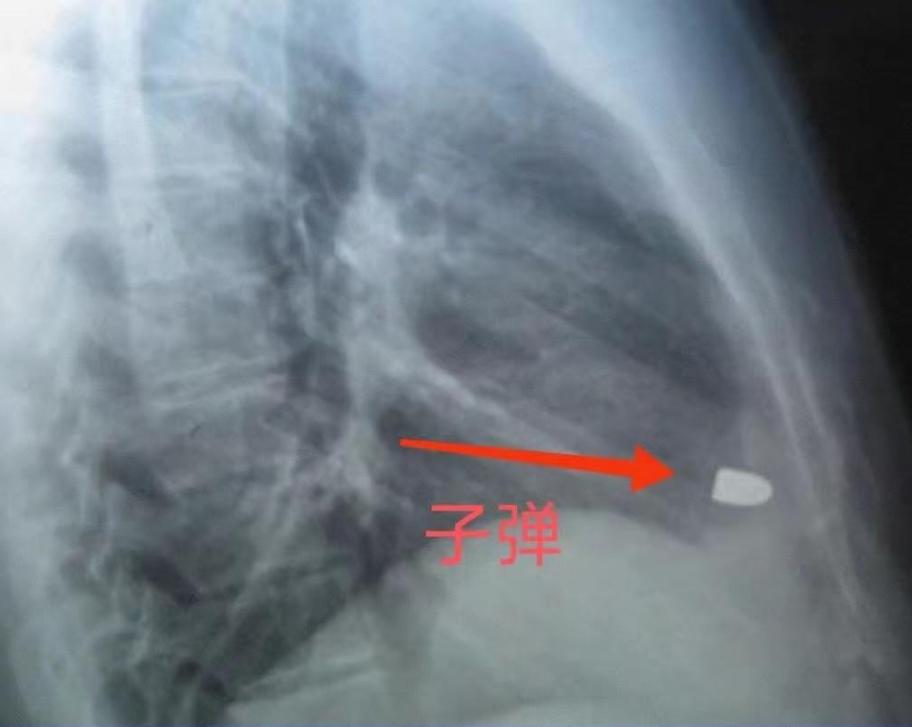

[太阳]1995年,湖南怀化的水果商符桂林去乡下收购橘子时,在路上不幸遇到了土匪,在打斗的过程中,土匪掏出手枪,对着符桂林开了两枪。一枪穿透了他的腿部,另一颗则击中了胸腔,可送到医院时,医生却没有在他的胸腔里找到这枚子弹。   上世纪90年代,符桂林乘船去收橘子,却在偏远的河道上撞上了土匪,混乱中,一声枪响,他应声倒地,等他再次醒来,人已经在县医院了。   医生告诉他,腿上是贯穿伤,子弹穿过去了,但射进右肋的那颗,却怎么也找不到,手术中,医生在他胸口的伤口里反复探查,就是没发现子弹的踪迹。   奇怪的是,符桂林的生命体征一直很稳,器官功能也正常,医生只能推测,那颗子弹可能撞到骨头后弹了出去,或者卡在表层后来自己掉了,为了防止感染,他们只能先将伤口缝合,就这样,这颗子弹在医学记录里,第一次“人间蒸发”了。   出院后的符桂林,总觉得身体不对劲,他的体力大不如前,干点重活就全身没力气,心口也时常隐隐作痛,最吓人的是,他的心跳有时会毫无征兆地飙升,最高能冲到每分钟170多次。   家里人不让他再干重活,他自己也成了县医院的常客,可心电图做了不少,医生查来查去,都说没什么大问题,只诊断是枪伤后遗症的正常反应,给他开点控制心率不齐的药,让他回家休养。   于是,在长达十几年的时间里,这颗子弹的真实存在,被巧妙地伪装成了“陈年旧伤”的各种症状。   直到2009年,因为父亲去世,符桂林操劳过度,心脏的老毛病愈发严重,他再次来到县医院,这次终于做了CT扫描。   影像出来,医生在他左侧胸腔发现了一个白色异物,然而,这个戏剧性的发现,却被医生一句不经意的话带偏了:“你是不是衬衫上有什么金属纽扣?”   医生甚至告诉他,心肺功能一切正常,但符桂林总觉得不对劲,他坚持脱掉衬衫,又做了一次,那个白色异物,依然顽固地待在原地。   这下医生也严肃起来,通过侧面CT和动态透视,真相终于大白:那是一个长约13毫米、直径7毫米的子弹头,而且它正随着心脏同频率地搏动着!   这个惊人的发现,让县医院的医生束手无策,符桂林被紧急送往省城长沙的中南大学湘雅医院,长沙的专家们看到片子时,都惊得说不出话,直呼这是个奇迹。   手术台上,当医生切开符桂林的心包,更不可思议的一幕出现了:他的心脏表面非常光滑,完全找不到任何陈旧的弹孔或伤痕,那颗子弹到底是怎么进去的?   医生们推测,子弹可能是从心脏右后方,穿过了右心房和右心室,最终精准地停在了左、右心室交界处厚约1厘米的心肌里,它被厚实的心肌牢牢包裹着,甚至已经被磨得有些变形。   这个位置惊险到了极点,再往前偏一点点,就会穿破心肌进入左心室,后果不堪设想。   北京的轻武器权威检测中心对此也进行了相关分析,这枚弹头虽然是六四手枪的专用子弹,但经过鉴定,专家推断它是一颗火药能量不足的劣质仿制品。   正是因为“伪劣”,它的威力大打折扣,射入人体后速度锐减,据估算,当它抵达符桂林的心脏时,速度已不足每秒100米,失去了致命的穿透力。   而心脏肌肉非凡的弹性,又起到了绝佳的缓冲和包裹作用,这才导致一颗威力不足的伪劣子弹,一个恰到好处的落点,再加上一颗展现出惊人修复力的心脏,让这颗子弹停留在身体里14年。 信息来源:搜狐新闻《“你真是命大。”1995年,一名男子被劫匪射了两枪,医生却只找到一颗子弹。14年后,子弹竟出现在意想不到的地方》